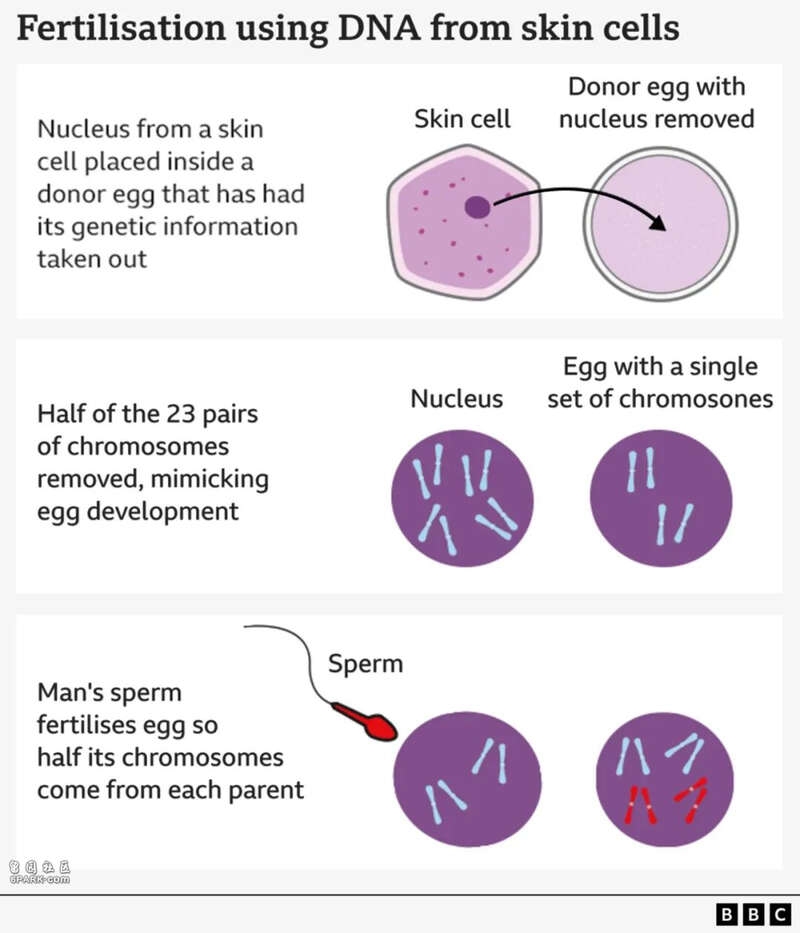

第一步,他们从一位志愿者的皮肤细胞中取出细胞核。里面装着全部遗传密码,也就是你全身上下的“蓝图”。

第二步,把这个细胞核塞进一个“空壳”卵子里。这个卵子原本的遗传物质已经被清空,就像清空内存准备重装系统。

听起来有点耳熟?对,就是和1997年诞生的克隆羊“多莉”用的是同一个核移植技术(SCNT)。

但不同之处是——多莉是克隆,而这里是想要制造一枚“可以重新组合染色体的真卵子”。

但问题随之来了:皮肤细胞有46条染色体,卵子却只能有23条。那怎么减半?

于是,科学家开发了一种新型细胞处理法,给它起了个酷酷的名字——“mitomeiosis”(米分裂),结合了有丝分裂(mitosis)和减数分裂(meiosis)的特征。

说白了,这就是一次“劝退计划”——劝细胞把自己的一半染色体扔掉。